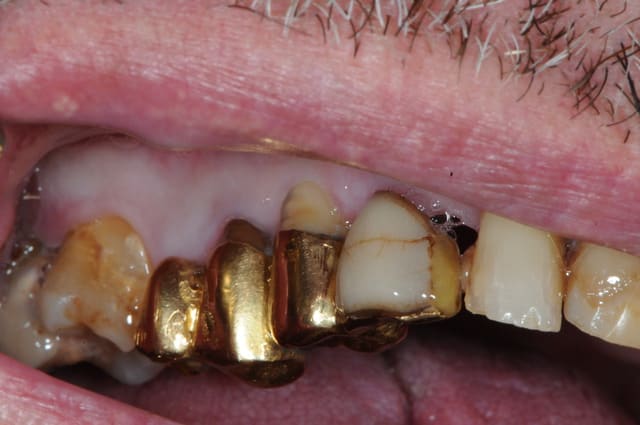

enfin des céramiques esthétiques et adaptées à l'âge du patient. Super.

Sur la photo "5658", il y a rougeur importante sur la

crête/gencive. Je crois que ton occlusion est trop forte. Dommage qu'il manque un appui plus postérieur dans ce coin.

L'ensemble st quand même très bien.

mais non, c'est une photo avant juste avant la pose du nouvel appareil. ici, la gencive est un peu traumatisée par le vieux partiel résine qui servait de cache misère.